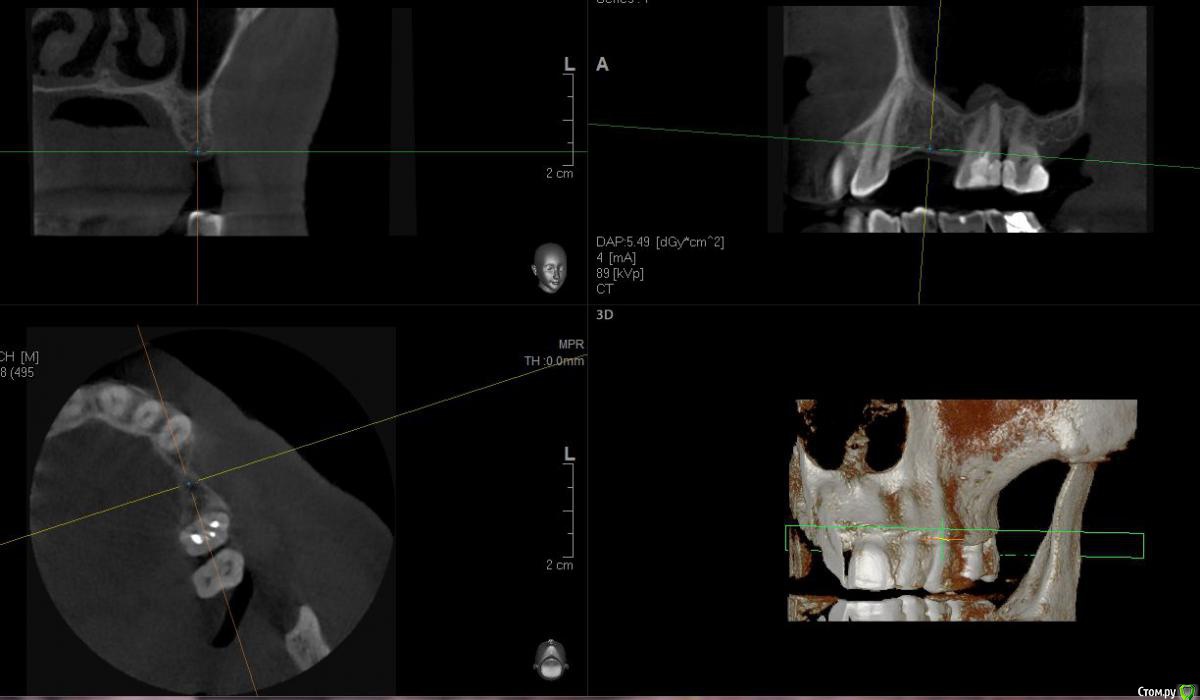

sugaka30 Опубликовано 7 января, 2017 Автор Поделиться Опубликовано 7 января, 2017 (изменено) Сделал Кт Может кто прокоментирует Не пора ли мне Пора? А то что то мне все плохеет https://yadi.sk/d/RXxAPdk237XVpi Заранее спасибо Изменено 7 января, 2017 пользователем sugaka30 Ссылка на комментарий

sugaka30 Опубликовано 7 января, 2017 Автор Поделиться Опубликовано 7 января, 2017 И скажите все таки есть перфо материала в гайморову или пронесло? Ссылка на комментарий

sugaka30 Опубликовано 22 января, 2017 Автор Поделиться Опубликовано 22 января, 2017 Проконсультируйте пожалуйста по этим срезам А то местный хирург не может понять что не так Ссылка на комментарий

St. Опубликовано 22 января, 2017 Поделиться Опубликовано 22 января, 2017 Скрины кт в обл леченного зуба Ссылка на комментарий